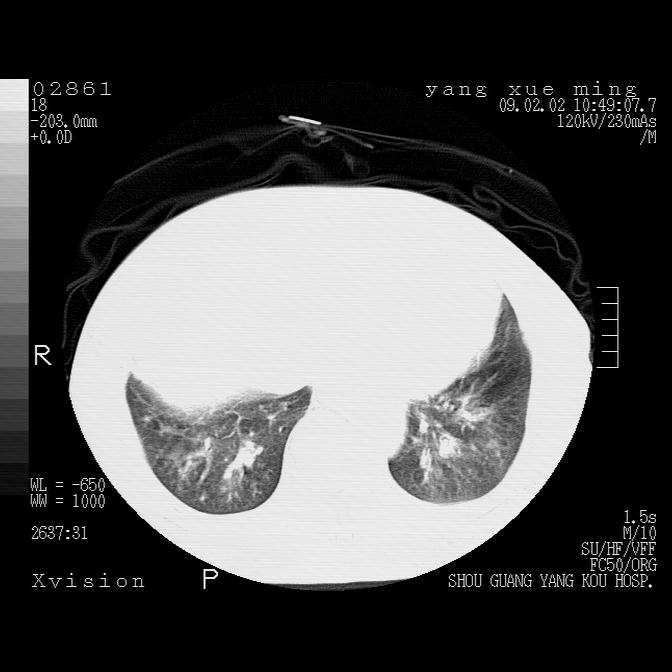

以下是引用zbp537在2009-2-3 19:08:00的发言:[br]我诊断为肺泡性肺水肿。[br]诊断依据:[br]1、心影普遍增大,肺血管增粗,并见絮状高密度影,肺门改变显著。[br]2、临床上表现胸闷咳嗽,无发烧,不是一个典型的肺部感染的病史。

以下是引用lkc8963在2009-2-3 20:11:00的发言:[br]1)右上肺陈旧病灶。2)右下肺团块及团片影,影像表现符合感染。3)左心增大,左冠脉钙化,符合冠心病。4)双侧肺门扩大,以左侧为著,肺动脉干略粗,左上肺局限性气肿,为谨慎起见,需除肿瘤,建议增强。

以下是引用lkc8963在2009-2-3 20:11:00的发言:[br]1)右上肺陈旧病灶.2)右下肺团块及团片影,影像表现符合感染.3)左心增大,左冠脉钙化,符合冠心病.4)双侧肺门扩大以左侧为著,肺动脉干略粗,左上肺局限性气肿,为谨慎起见,需除肿瘤,建议增强.